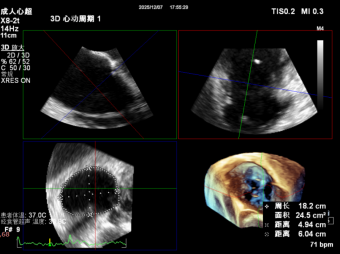

CTA Assessment:

- Tricuspid annulus circumference: 20.1cm, area: 31.7cm² (massive tricuspid annulus);

- Septal-lateral diameter: 63mm, antero-posterior diameter: 63mm;

2. Annuloplasty Effect: